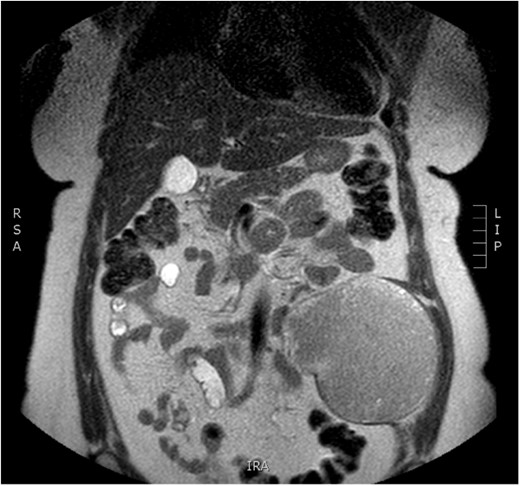

Physical examination revealed a painless, mobile parietal mass on the left anterior abdominal wall, more prominent during cough, of ~13 cm in diameter, with smooth contour and without skin involvement. Laboratory examination including cancer marks showed results within normal limits; hydatid serology (IgG antibodies) was also negative. As ultrasonography results were inconclusive, further imaging with magnetic resonance imaging (MRI) revealed a sizable cystic mass measuring 10 × 13.4 × 11.7 cm, located in the left anterior abdominal quadrant, in the paraumbilical region, between the left internal oblique and the transversus oblique muscle, with projection to the inferior surface of the rectus abdominis. The mass was characterized as a thin-walled cystic lesion, with delayed uptake of intravenous contrast of the wall. High signal intensity was observed on T1-weighted images and low signal intensity on T2-weighted images, with high probability of neoplasia or bleeding (Figs 1–3). No other abdominal or pulmonary lesions were present.

Preoperative MRI—axial plane. T1 weighted image. High sign density of the lesion.

Preoperative MRI. T2 weighted image. Low sign density of the lesion.